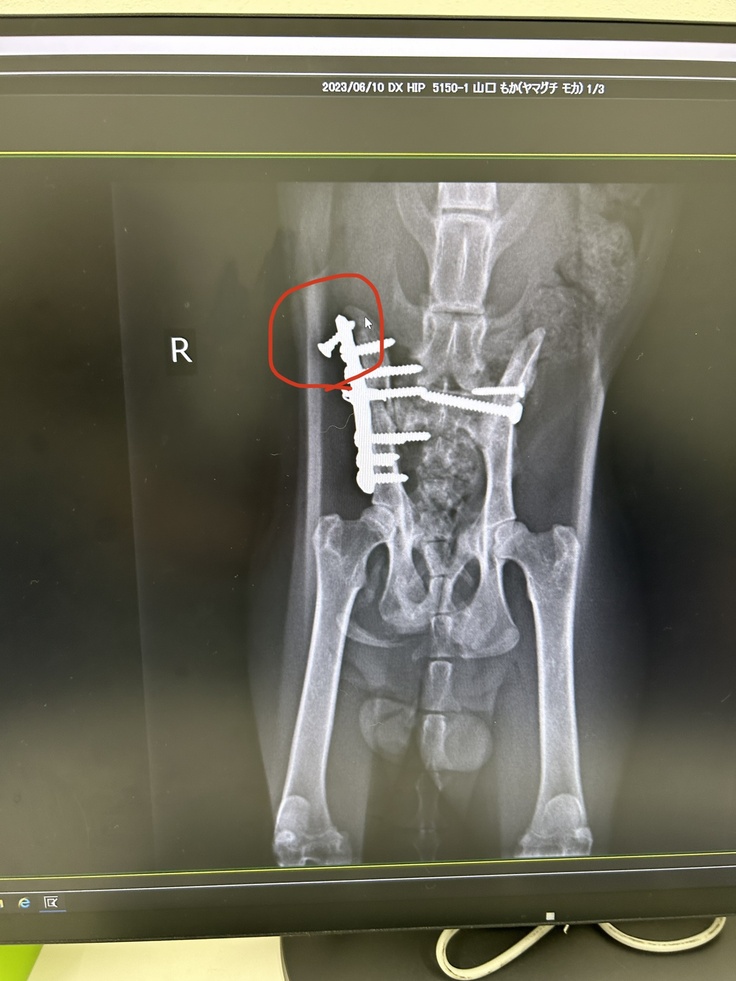

レントゲンを撮っていただくと…

赤丸部分のボルトが外れかかっていました。

少しずつ動けるようになって

負担がかかってしまったのか…

外れかかっているところの炎症や痛みによる

発熱、震えがあり

歩行もボルトが外れかかってしまう前より

歩きにくそうになってしまっているとのことで…